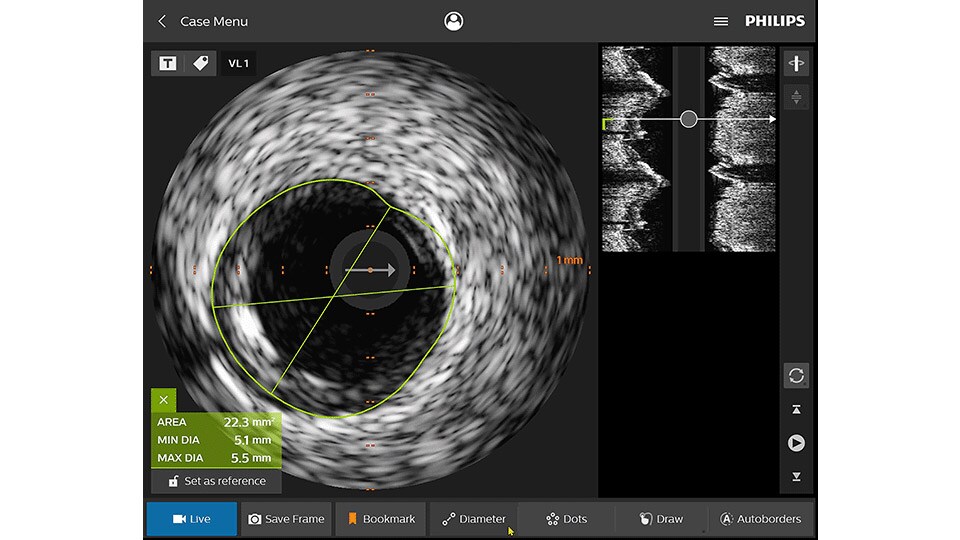

Intravascular ultrasound (IVUS) provides images from within the vessel to accurately assess and optimize your treatment plan.

New invasive imaging techniques and co-registration software allows PCI to be performed with limited amounts of contrast, even with zero-contrast use, to reduce the risk of CI-AKI for all patients, and especially those with renal insufficiency.

Philips PCI guidance solutions incorporate non-invasive and adjunctive IVUS and iFR modalities, requiring less contrast for proper diagnosis.